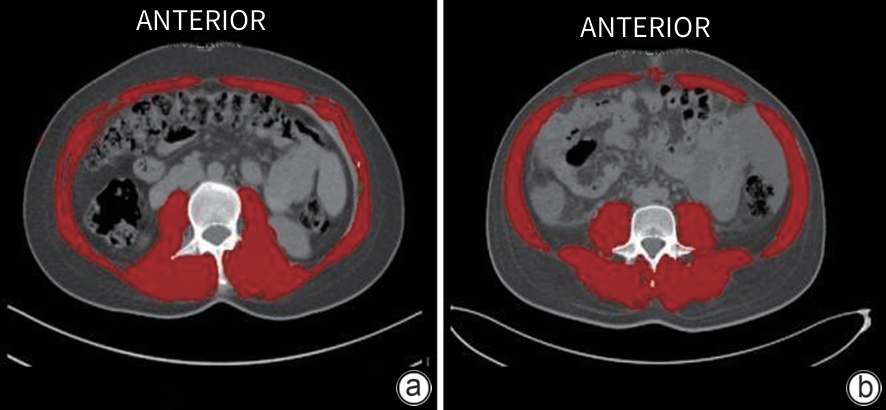

Application of a multimodal model based on radiomics and 3D deep learning in predicting severe acute pancreatitis

Xianglin DING, Xin CHEN, Meiyu CHEN, Yiping SHEN, Yu WANG, Minyue YIN, Kai ZHAO, Jinzhou ZHU

2025, 41(10): 2110-2117. DOI: 10.12449/JCH251022

Abstract:

Objective  To investigate the application value of a multimodal model integrating radiomics features, deep learning features, and clinical structured data in predicting severe acute pancreatitis (SAP), and to provide more accurate tools for the early identification of SAP in clinical practice.  Methods  The patients with acute pancreatitis (AP) who attended The First Affiliated Hospital of Soochow University, Jintan Hospital Affiliated to Jiangsu University, and Suzhou Yongding Hospital from January 1, 2017 to December 31, 2023 were included. Related data were collected, including demographic information, previous medical history, etiology, laboratory test data, and systemic inflammatory response syndrome (SIRS) within 24 hours after admission, as well as imaging data within 72 hours after admission, while related scores were calculated, including Ranson score, modified CT severity index (MCTSI), bedside index for severity in acute pancreatitis (BISAP), and systemic inflammatory response syndrome, albumin, blood urea nitrogen and pleural effusion (SABP) score. The model was constructed in the following process: (1) three-dimensional CT images were used to extract and identify radiomics features, and a radiomics classification model was established based on the extreme gradient Boost (XGBoost) algorithm; (2) U-Net is used to perform semantic segmentation of three-dimensional CT images, and then the results of segmentation were imported into 3D ResNet50 to construct a deep learning classification model; (3) the predicted values of the above two models were integrated with clinical structured data to establish a multimodal model based on the XGBoost algorithm. The variable importance plot and local interpretability plot were used to perform visual interpretation of the model. The independent samples t-test was used for comparison of normally distributed continuous data between groups, and the Mann-Whitney U test was used for comparison of non-normally distributed continuous data between groups; the chi-square test or Fisher’s exact test was used for comparison of categorical data between groups. The receiver operating characteristic (ROC) curve was plotted for each model and existing scoring systems, and the area under the ROC curve (AUC) was calculated to assess their performance; the Delong test was used for comparison of AUC.  Results  A total of 609 patients who met the criteria were included, among whom 114 (18.7%) developed SAP. In this study, the data of 426 patients from The First Affiliated Hospital of Soochow University was used as the training set, and the data of 183 patients from Jintan Hospital Affiliated to Jiangsu University and Suzhou Yongding Hospital were used as the independent test set. The multimodal model had an AUC of 0.914 in the test set, which was significantly higher than the AUC of traditional scoring systems such as MCTSI (AUC=0.827), Ranson score (AUC=0.675), BISAP (AUC=0.791), and SABP score (AUC=0.648); in addition, the multimodal model showed a significant improvement in performance compared with the radiomics classification model (AUC=0.739) and the deep learning classification model (AUC=0.685) (the Delong test: Z=-3.23, -4.83, -3.48, -4.92, -4.31, and -4.59, all P <0.01). The top 10 variables in terms of importance in the multimodal model were pleural effusion, predicted value of the deep learning model, predicted value of the radiomics model, triglycerides, calcium ions, SIRS, white blood cell count, age, platelets, and C-reactive protein, suggesting that the above variables had significant contributions to the performance of the model in predicting SAP.  Conclusion  Based on structured data, radiomic features, and deep learning features, this study constructs a multicenter prediction model for SAP based on the XGBoost algorithm, which has a better predictive performance than existing traditional scoring systems and unimodal models.